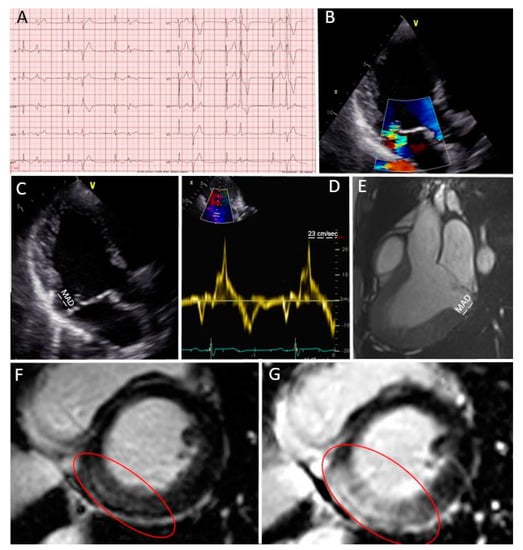

Case 2 (Figure 3): Secondary prevention ICD implantation after cardiac arrest and multi-modality imaging work-up

Figure 3.

Case 2: Secondary prevention ICD implantation after cardiac arrest and multi-modality imaging work-up. (A) Patient’s ECG; (B) moderate mitral regurgitation during color Doppler transthoracic echocardiography; (C) bileaflet prolapse with MAD (in white); (D) MAD measured in a steady-state free precession three-chamber view during CMR; (E,F) a large zone of fibrosis in the basal and mid-lateral wall in LGE sequences (red circle).

A 40 year-old man was known for mitral valve prolapse since adolescence and was periodically followed by a cardiologist. Baseline ECG was not remarkable (Figure 3A), mitral regurgitation was moderate during echocardiography (Figure 3B), and the patient was asymptomatic in his daily life. However, he presented several “red flags” during echocardiography, in particular, the presence of a bileaflet mitral valve prolapse with MAD (Figure 3C). Then, the patient suffered a cardiac arrest on ventricular fibrillation during jogging and he was admitted to the emergency room. Coronary angiography was normal. Moderate mitral regurgitation was confirmed upon urgent echocardiography. During continuous ECG monitoring in the intensive care unit, several ventricular extrasystoles were noticed. CMR was then performed, confirming the presence of MAD (Figure 3D) and demonstrating a large zone of fibrosis in the basal inferior wall (Figure 3E,F, red circle). The extracellular volume determined by T1 mapping was high in all basal left ventricular segments. The patient then underwent an EPS, which showed the induction of ventricular tachycardia and ventricular fibrillation. A subcutaneous ICD was finally implanted as a secondary prevention measure, and treatment with 80 mg/day of nadolol was started. No arrhythmic events were present at the one-year follow-up.